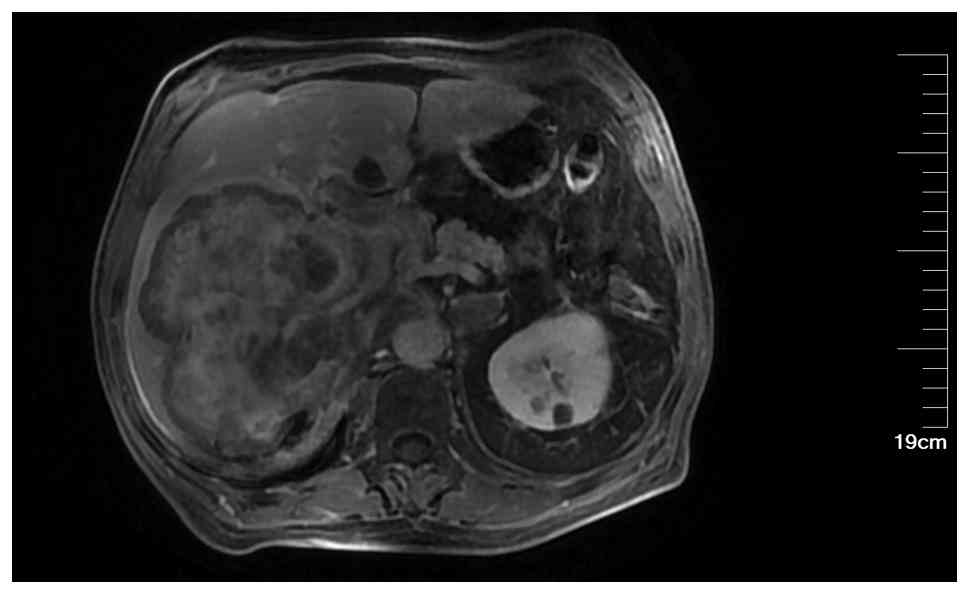

Ultrasound of the liver, gallbladder, pancreas, spleen and kidneys revealed a large solid mass in the liver (Fig. 1), a hypoechoic lesion between the upper pole of the right kidney and the posterior segment of the right lobe of the liver and a hypoechoic nodule in the first hepatic portal area. The liver ultrasound findings were consistent with chronic liver disease. An enhanced MRI of the liver suggested a high likelihood of hepatocellular carcinoma (HCC) in the right lobe (Fig. 2), with multiple metastatic tumors in the liver, bilateral adrenal glands and pancreas. A chest CT scan with three-dimensional reconstruction indicated a mass in the left hilum and left upper lobe of the lung, raising concerns for a malignant lesion with obstructive inflammation. The patient underwent ultrasound-guided biopsy of the liver mass and lymph nodes in the left supraclavicular region. Pathological examination (Fig. 3), supported by immunohistochemical staining performed according to the standard diagnostic protocols of the Department of Pathology at Hebei General Hospital, confirmed the diagnosis of SCNEC. Immunohistochemical staining (the full results are based on pathology reports rather than retrievable images, as the pathology reports cannot be published) included pan-cytokeratin (CKpan) (+), vimentin (−), chromogranin A (CgA) (+), synaptophysin (Syn) (+), cluster of differentiation 56 (CD56) (+), thyroid transcription factor-1 (TTF-1) (+), arginase-1 (−), hepatocyte paraffin 1 (HepPar-1) (−) and P53 (+++), and Ki-67 showing an active region of ~70% positive.

Case 1: Ultrasound image of the liver.

A large hyperechoic mass was identified in the right lobe of the

liver, measuring ~12.8×12.8×10.7 cm, with ill-defined borders and

heterogeneous internal echotexture.

Figure 1.

Case 1: Ultrasound image of the liver. A large hyperechoic mass was identified in the right lobe of the liver, measuring ~12.8×12.8×10.7 cm, with ill-defined borders and heterogeneous internal echotexture.